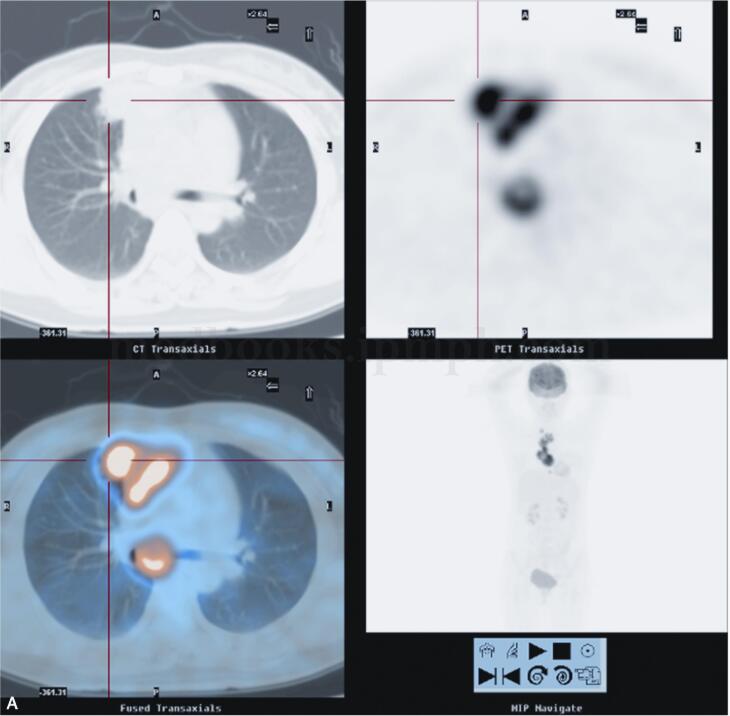

2010年5月10日于我院18F-FDG PET/CT检查:纵隔内及右肺上叶前段病变,代谢异常升高,考虑慢性感染性疾病可能性大(结核肉芽肿?),请结合临床,进一步完善结核相关检查,必要时纵隔镜活检以除外恶性病变(图2)。

图2 PET/CT示右肺上叶前段纵隔旁见高密度实变影,内见充气支气管影,FDG代谢放射性分布异常浓聚(SUVmax=12.4)。前纵隔内见软组织密度肿块影,最大截面积约为5.2cm×3.0cm,其内密度不均,见低密度坏死区,实质区FDG代谢放射性分布异常浓聚(SUVmax=15.0),邻近心包;右锁骨上、前上纵隔、主肺动脉窗,气管叉下(其内见钙化灶)及心包右旁见肿大淋巴结影,部分融合趋势,FDG代谢放射性分布异常浓聚